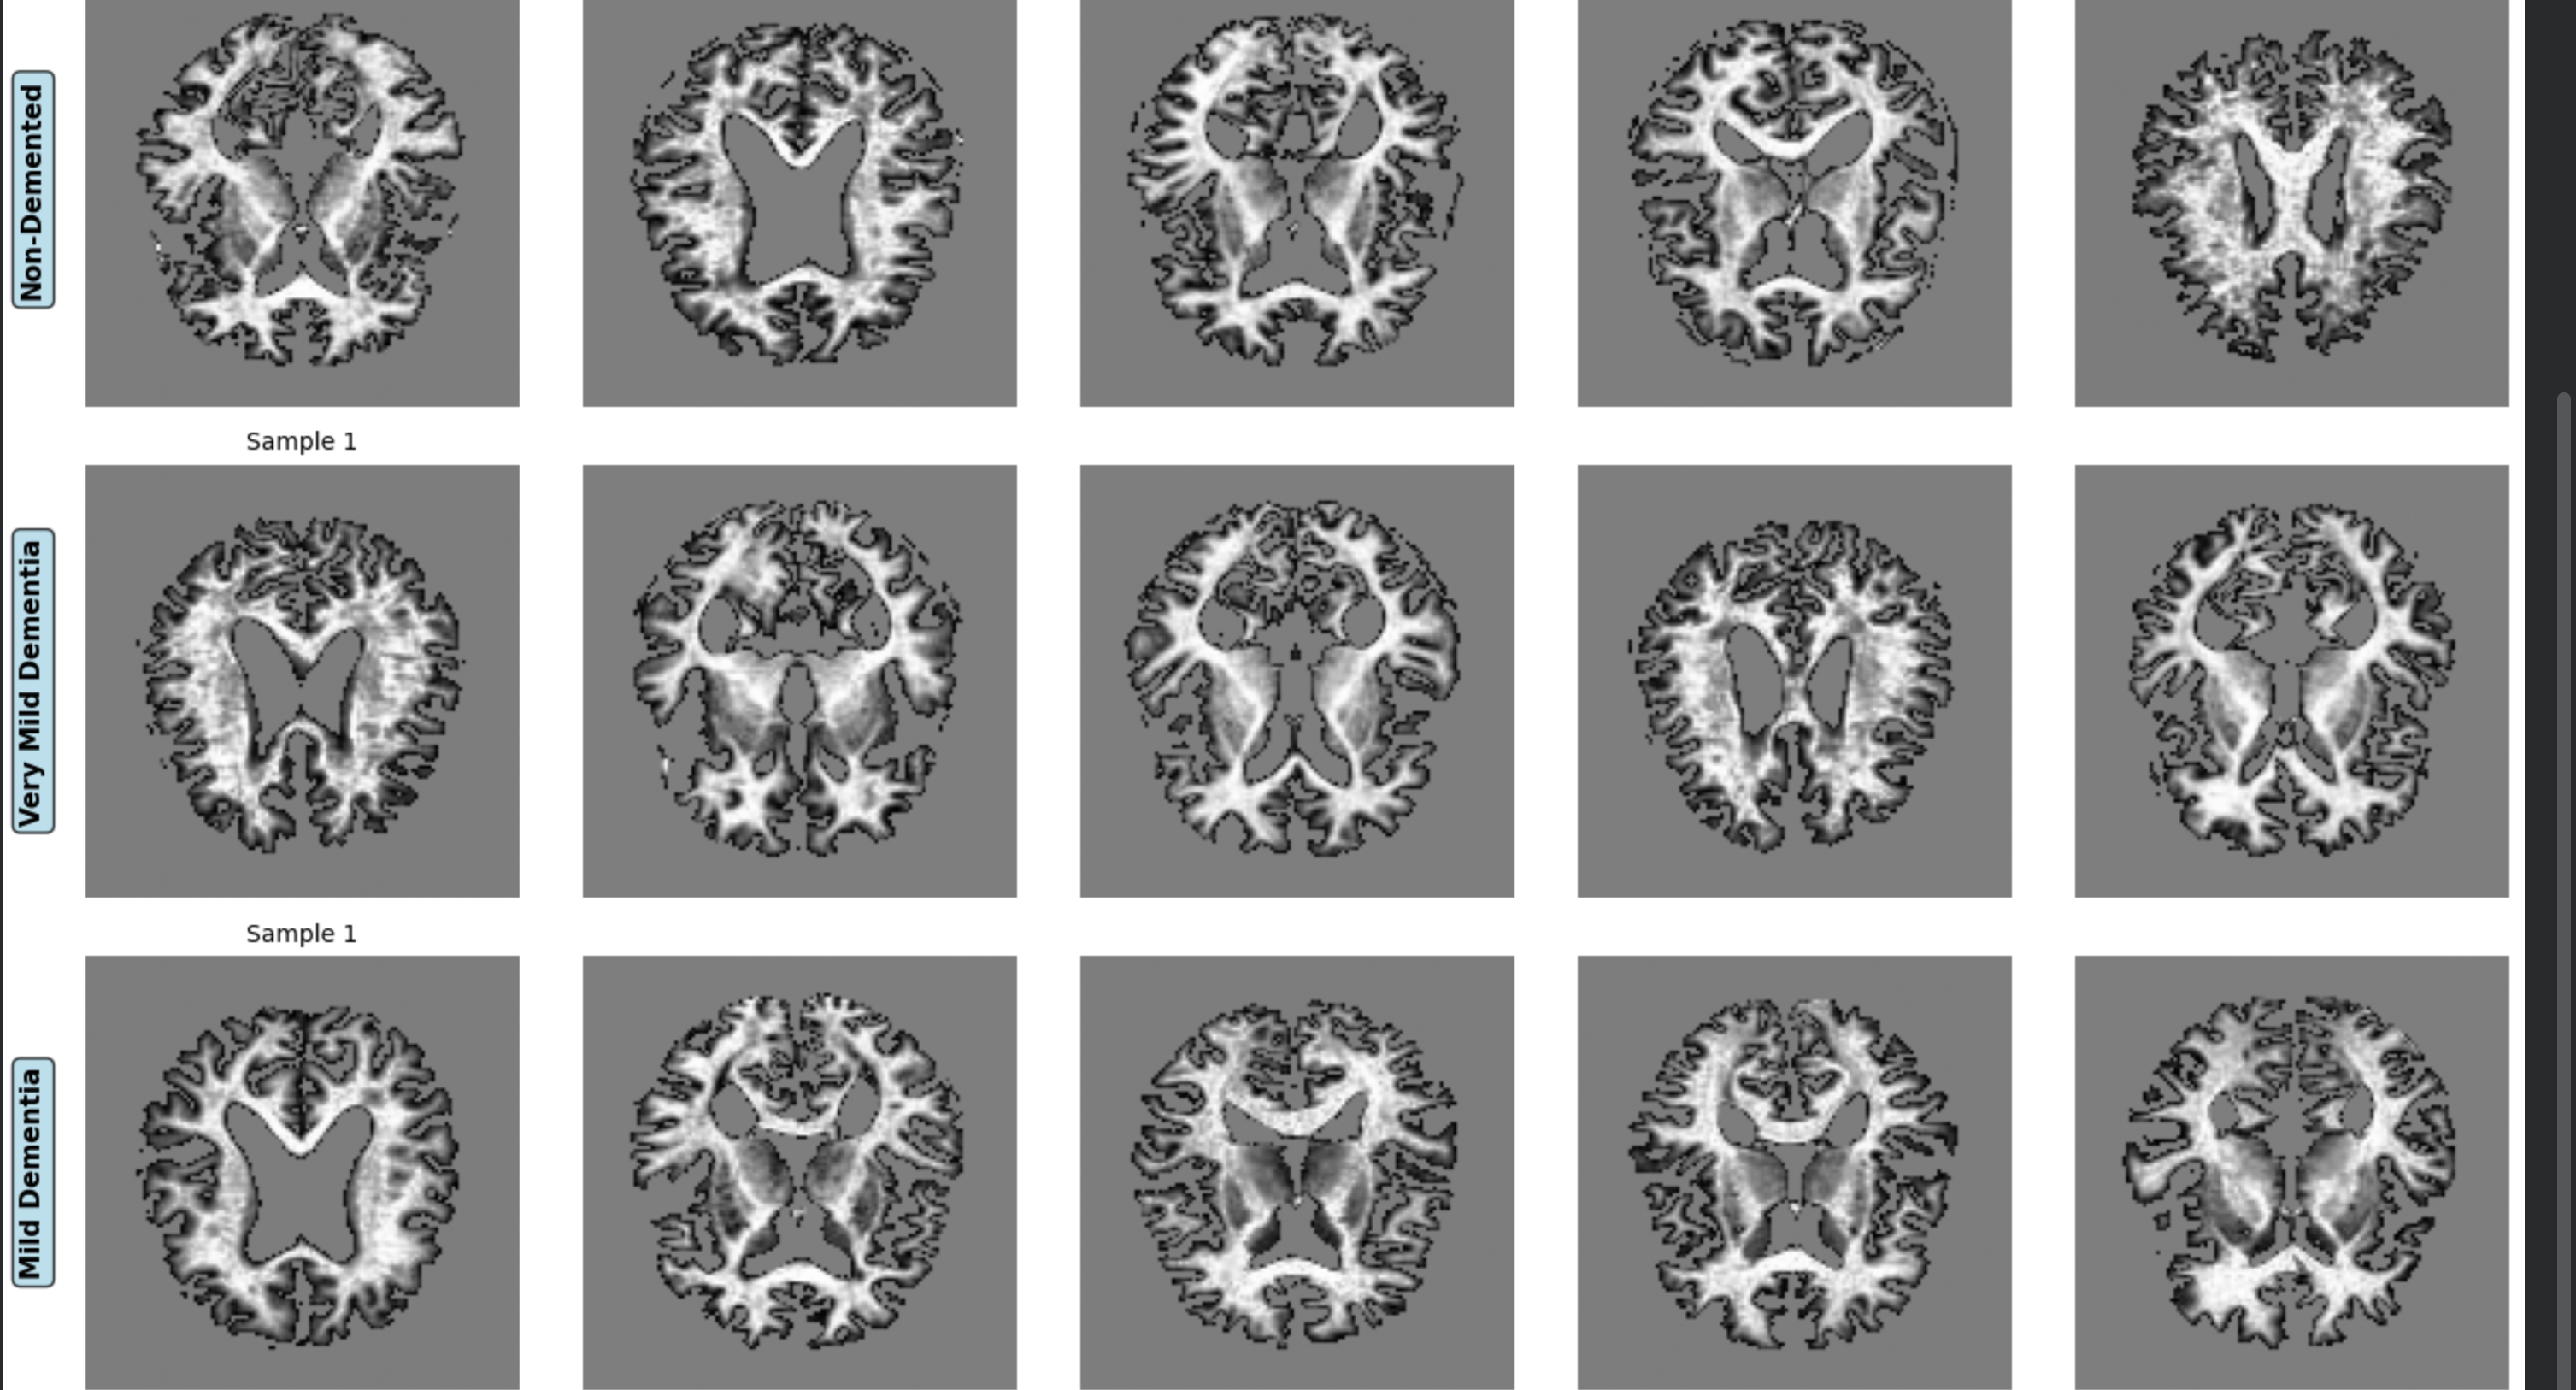

Sample MRI Images Grid by Class

Stage-Level Classification: Classifies MRI scans into four clinically defined categories—Non-Demented, Very Mild Dementia, Mild Dementia, and Moderate Dementia.